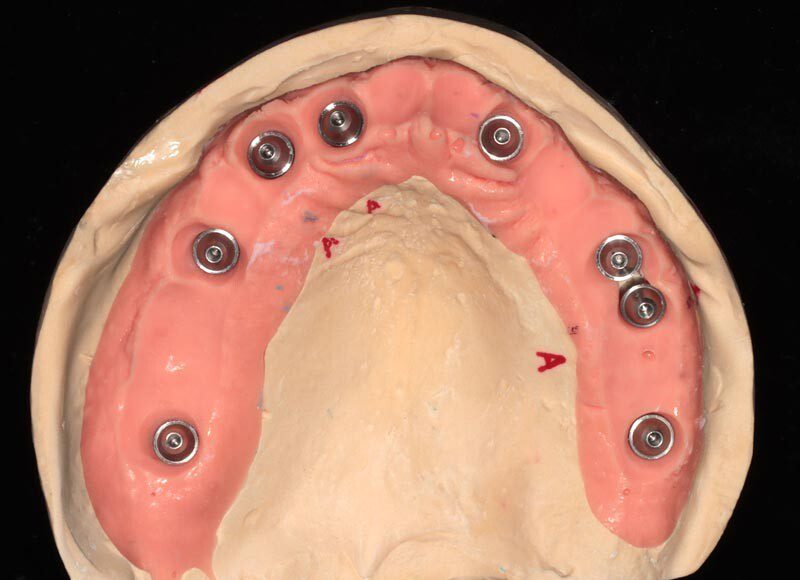

Three months post, first surgery the patient returns for implant uncovering and these are the impression copings preparing for the fixed temporary bridge.